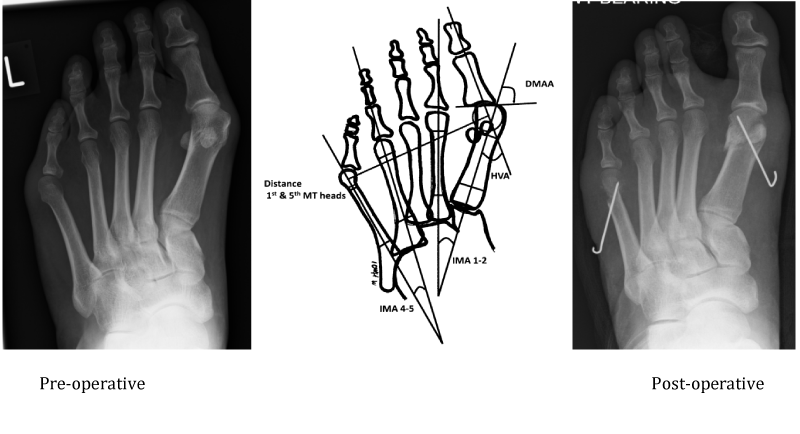

This series study included 9 symptomatic patients (12 feet) with splayfoot deformities. The patient's pre-operative and post-operative weight bearing X-rays (Figure 1) were independently assessed by senior orthopaedic registrars FA and SR. The hallux valgus angles (HVA), 1st and 2nd intermetatarsal angles (IMA 1-2), distal metatarsal articular angles (DMAA), 4th and 5th intermetatarsal angles (IMA 4-5), maximum widths of the 1st and 5th metatarsal heads and the maximum distance between the centers of the 1st and 5th metatarsals were calculated. The change in the angles and distances post-operatively were then assessed for statistical significance using non-parametric paired t-tests. Patients were followed up and assessed at 6 months and at 48 months post-operatively. The operative procedure was carried out by the senior author.

Figure 1 Pre-operative X-rays, diagram to calculate deformity angles and post-operative X-rays following corrective osteotomies.